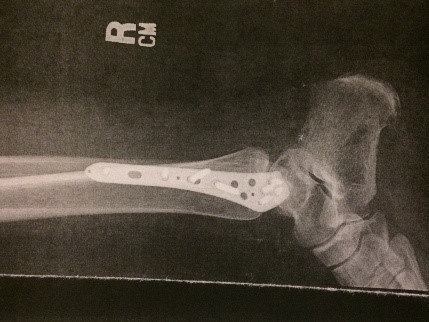

Attached is a picture of my foot about 30 days after a team of surgeons re-attached it following a horrific car accident; I had just gotten my cast removed.

I was airlifted to the nearest Trauma Hospital – where a group of remarkable surgeons spent hours re-attaching my foot to my ankle.  In addition, they fixed my fibula and tibia bones which were broken (and needed a plate screwed to them), and inserted a rod in my broken femur bone all the way from my hip to my knee.  Finally they put a plate and screws in the humerus bone in my right arm; three fractured ribs were left to heal themselves.

2. About 4 weeks later (second week of September) I started physical therapy at the local hospital.  My insurance company had approved 8 weeks of therapy three times a week. I was nicknamed the Bionic Woman because of all the hardware I had implanted in my body.